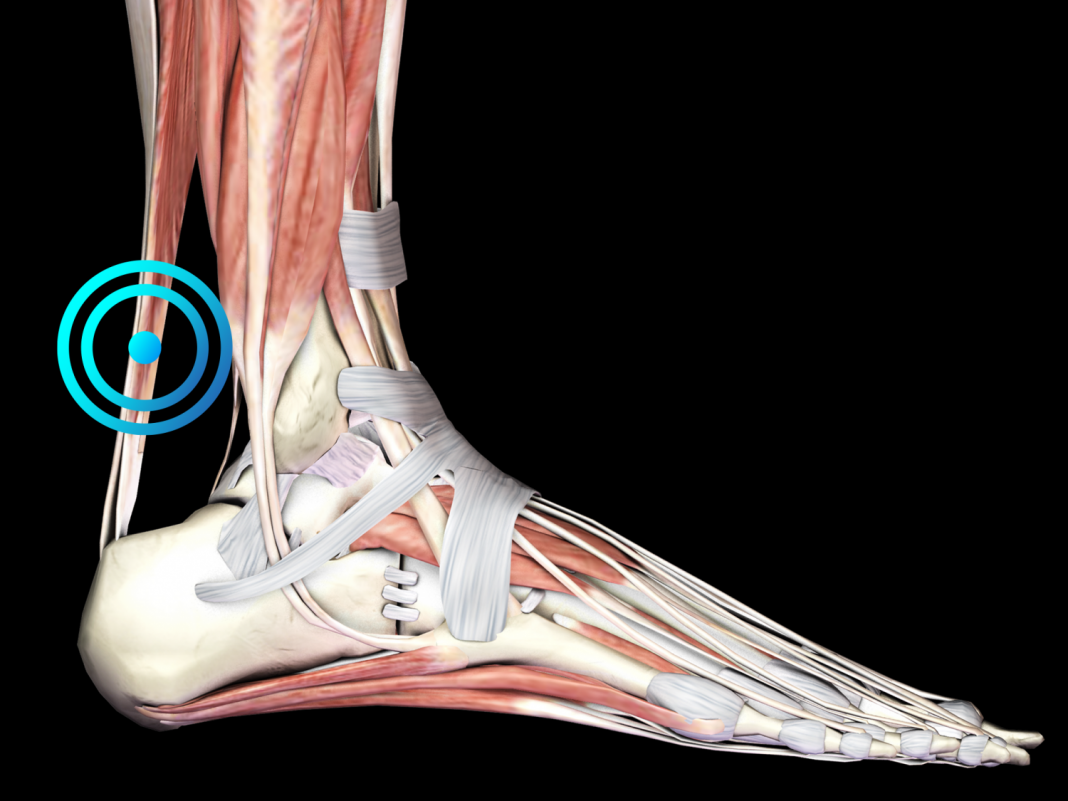

3Es muy común sufrir de tendinopatías

Es una de las más comunes, originándose en los tendones y es porque los músculos se sobrecargan de tensión al hacer presión sobre el hueso para realizar el movimiento. Esta es la tendinitis rotuliana por pedalear por mucho tiempo, subir caminos con mucho esfuerzo.

También están otras como: tendinitis del cuádriceps, tendinitis de isquiotibiales, tendinitis de la banda iliotibial y tendinitis del tendón de Aquiles. Por ello es importante corregir las malas posturas y cumplir un reposo prolongado para recuperarse.